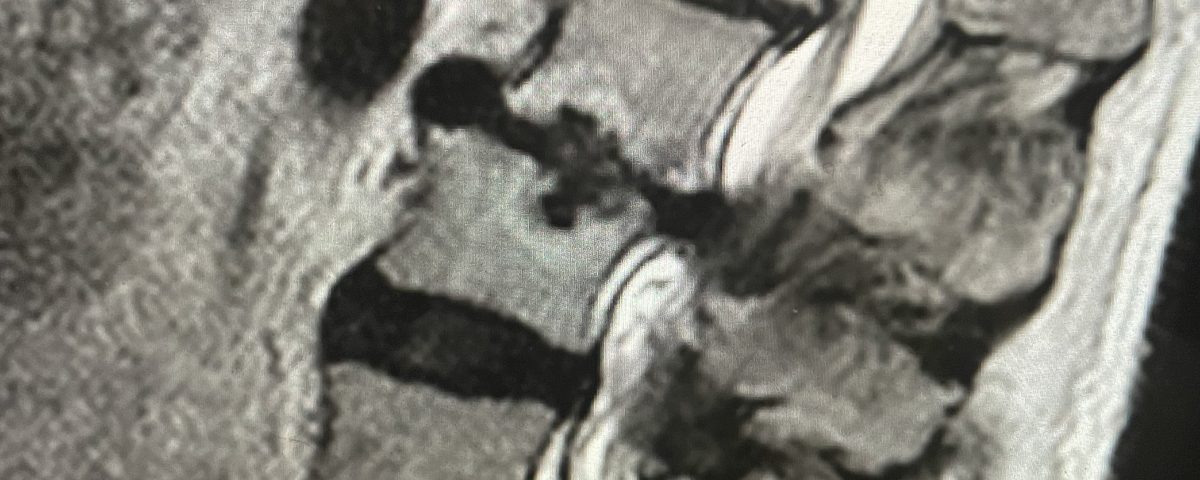

Figure 2. T2-weighted sagittal and axial MRIs demonstrating severe L3-4 stenosis and an L5-S1 grade 1 spondylolisthesis and spondylolysis and L3-4 retrolisthesis. Note the anterior osteophyte formation at L2-3 with attempted autostabilization of segment.

He had mild proximal weakness of his hip flexors. He also had a history of diabetes, hypertension, and hypercholesterolemia. Imaging studies were obtained. Plain x-rays (Fig. 1) demonstrated a degenerative levoscoliosis with the apex of the curve at L2-3. Lumbar MRI (Fig. 2) showed severe degenerative disc disease with an L5-S1 grade 1 spondylolisthesis and a significant retrolisthesis at L3-4 with severe lumbar stenosis.